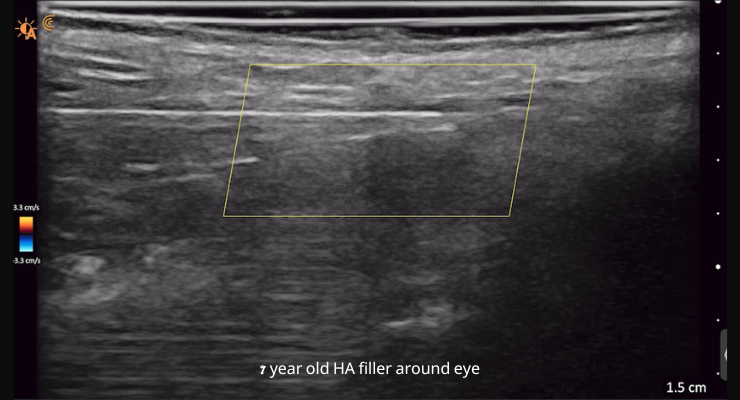

• הדמיה ברורה למיפוי של הרקמה ומניעה של חסימת כלי דם

• מאפשר טיפול בטוח להמסת חומר מילוי ו/או טיפול ואבחון סיבוכים אחרים